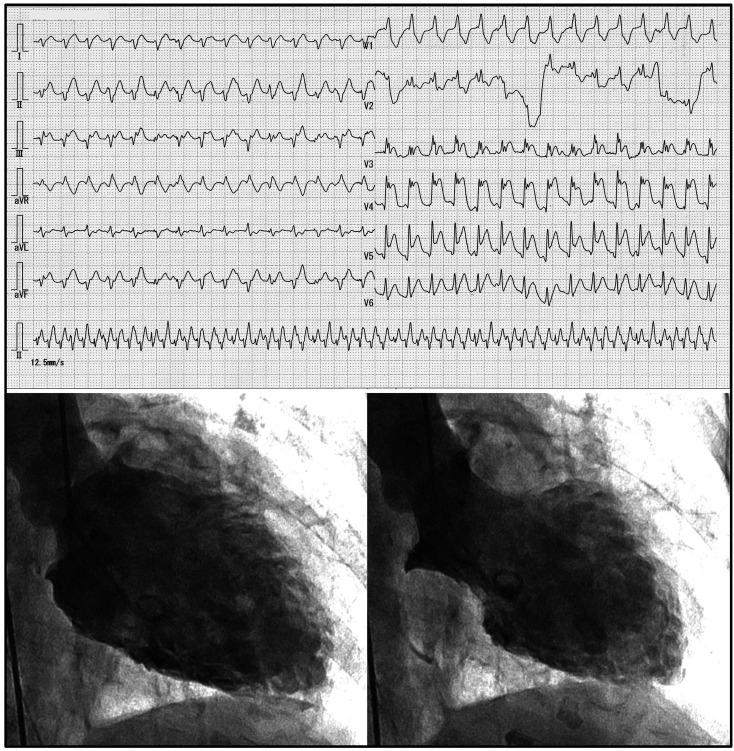

Cardiac arrest (CA) has been observed in some patients with Takotsubo syndrome (TTS), most of whom had CA at the initial presentation of TTS. The objective of this report was to discuss the factors underlying the onset of this syndrome. A 72-year-old woman with refractory antineutrophil cytoplasmic autoantibody-associated lung disease was referred to our hospital. Twenty minutes after bronchoscopic examination, cardiopulmonary arrest suddenly occurred. Resuscitation immediately resumed her heartbeat and spontaneous breathing. Subsequent 12-lead electrocardiography, echocardiography, and left ventricular angiography revealed TTS. This case indicates that bronchoscopy can cause severe TTS, especially in patients with systemic inflammation.

在一些应激性心肌病(TTS)患者中观察到心脏骤停(CA),其中大多数患者在TTS初次发病时就出现了CA。本报告的目的是探讨该综合征发病的潜在因素。一名72岁患有难治性抗中性粒细胞胞浆抗体相关性肺病的女性被转诊至我院。支气管镜检查20分钟后,突然发生心肺骤停。复苏立即恢复了她的心跳和自主呼吸。随后的12导联心电图、超声心动图和左心室血管造影显示为TTS。该病例表明,支气管镜检查可导致严重的TTS,尤其是在全身性炎症患者中。